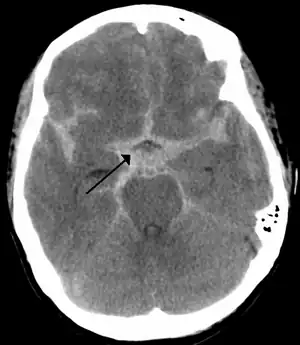

Subarachnoid bleed

If an aneurysm ruptures, blood leaks into the space around the brain. This is called a subarachnoid hemorrhage. Onset is usually sudden without prodrome, classically presenting as a "thunderclap headache" worse than previous headaches.[6][7] Symptoms of a subarachnoid hemorrhage differ depending on the site and size of the aneurysm.[7] Symptoms of a ruptured aneurysm can include:

Almost all aneurysms rupture at their apex. This leads to hemorrhage in the subarachnoid space and sometimes in brain parenchyma. Minor leakage from aneurysm may precede rupture, causing warning headaches. About 60% of people die immediately after rupture.[8] Larger aneurysms have a greater tendency to rupture, though most ruptured aneurysms are less than 10 mm in diameter.[7]